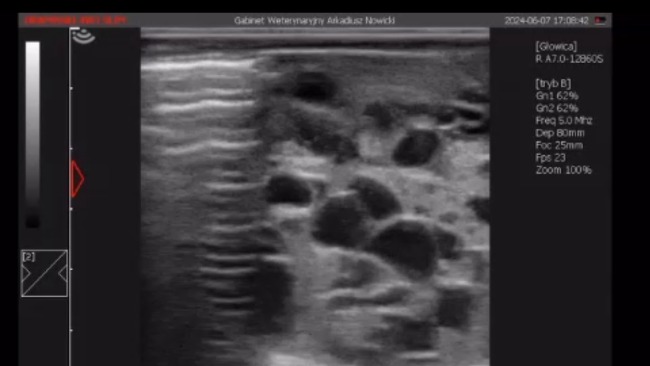

Niestety kiedy nastała wiosna i u klaczy rozpoczęły się ruje zachowanie Dionizy wobec innych klaczy zaczęło być podejrzane - zaczęła zachowywać się jak ogier skacząc na klacz Indi z próbą kopulowania. Niestety nie jest to normalne zachowanie dla klaczy, więc zrobiliśmy Doni usg jajników i moja intuicja mnie nie zawiodła (niestety) - jeden jajnik jest chory.

Jest to nowotwór niezłośliwy - guz z komórek ziarnistych (GCT) najczęstszy rodzaj nowotworu atakującego układ rozrodczy koni, w szczególności jajniki. Guzy te są często łagodne (nie rozprzestrzeniają się), jednak mogą ograniczać wydajność ze względu na powiązane problemy behawioralne i potencjalnie ból, w zależności od ich wielkości. Guzy te mogą również wpływać na zdolność rozrodczą klaczy ze względu na podwyższony poziom hormonów rozrodczych. Zazwyczaj nowotwór z komórek ziarnistych dotyczy tylko jednego jajnika, a drugi jajnik jest mniejszy i nieaktywny ze względu na hormony wytwarzane przez zajęty jajnik. Leczenie chirurgiczne polega na wycięciu w klinice.

Kochani załączam Wam zdjęcia z usg chorego jajnika wykonane przez dr Arkadiusza Nowickiego oraz kilka zdjęć Doni żebyście mogli sami poczuć moc miłości płynącą od tego konia.